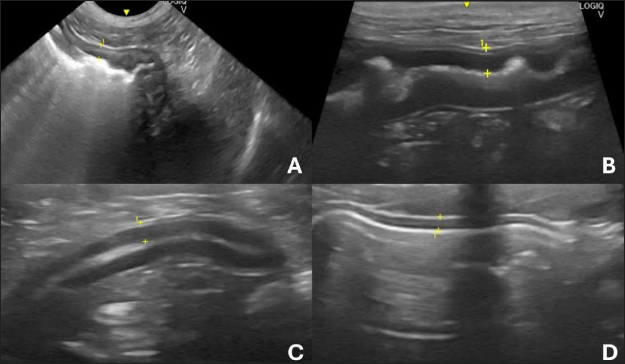

The duodenum (Fig. 1B) of a healthy dog can be differentiated from the jejunum (Fig. 1C) by USG because of its more superficial topography in the right epigastric region and because it is cranially close to the stomach (Fig. 1A). In addition, it is possible to observe the duodenal papilla as an anatomical reference if the image resolution is of high quality (Riedesel, 2015).

The ileum (Fig. 1D) was anatomically located in the craniomedial abdomen to the right of the ascending colon and cecum (Goggin et al., 2000). This intestinal segment can be visualized by USG in the right abdominal quadrant and is the most robust and bright submucosal layer in the image (Prestes et al., 2019). The jejunum can be found and evaluated by the US in practically every abdominal cavity (Goggin et al., 2000). Although the jejunal loops can be found and form an image during the evaluation of the other structures during the complete examination, systematic and detailed scanning of the jejunal segments is recommended (Larson and Biller, 2009).

Fig. 1. Ultrasound images of the gastrointestinal tract of healthy dogs. A: gastric body, B: duodenum, C: jejunum, D: ileum. All segments with wall thickness were measured using a cursor in the ultrasound machine software. 8 MHz microconvex transducer.